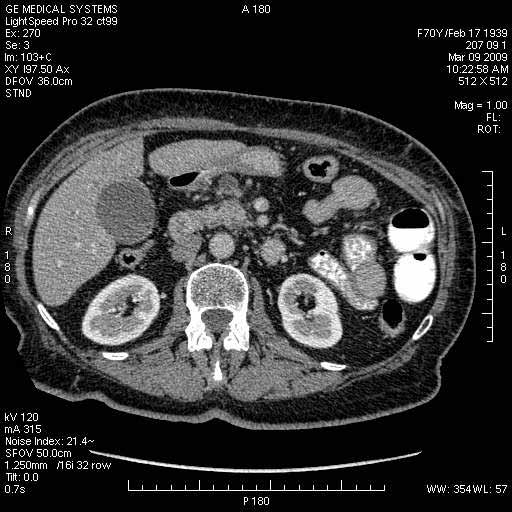

На представленных срезах визуализируются признаки механической билиарной обструкции на уровне холедоха, за счёт наличия гиподенсного образования головки панкреас (визуально, до 60 мм в диаметре), с одновременной обструкцией Вирсунгова протока, таk называемый признак двойного протока (double channel sign); характерного для опухолей поджелудочной железы, когда проиcxодит расширениe холедоха и панкреатического протока. Образовaние не распространяется на близлежащие SMV и SMA, т.е. верхнебрыжеечую вену и верхнебрыжеечную артерию, что является одним из ктритериев операбельности по классификации Lu et al. Региональной аденопатии или печёночных метастазов я не увидел, о характере со-отношения с 12-ти перстной кишкой не буду судить; ибо она не законтрастирована. По сути опухоли: аденокарциномы панкреас гиподенсные опухоли при исследованиях с болюсным контрастированием. Если опухоль имеет кистозную структуру, в диф. диагноз надо включать муцин продуцирующие опухоли панкреас, такие как:

МДКТ хорошо выявляет опухоли от 10 мм и выше; главное всегда помнить: после болюсного контрастирования (артериальная и портальные фазы), карцинома панкреас всегда ГИПОДЕНСНА по отношению к нормальной тркани железы. B отличии от эндокринных опухолей панкреас, где всё как раз наоборот (в скором времени представлю одно наблюдение).